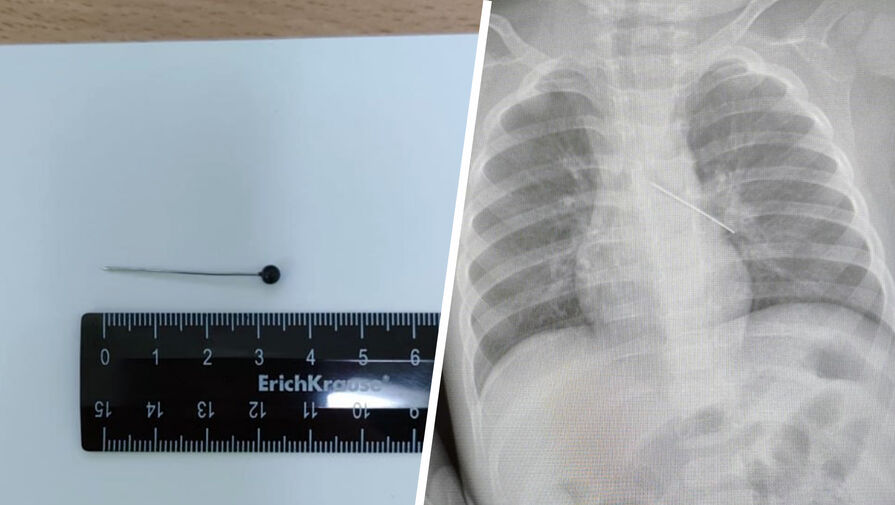

В ХМАО годовалый ребенок проглотил булавку

В Сургуте врачи спасли годовалого ребенка, проглотившего булавку

Врачи Центра охраны материнства и детства спасли 17-месячного ребенка, который из любопытства проглотил булавку. Об этом сообщила президент медицинского учреждения Лариса Белоцерковцева в Telegram-канале.

По словам медика, мать мальчика вовремя заметила беду и привезла ребенка в медицинское учреждение. Обследование показало, что инородный предмет зафиксировался в бронхах.

«Если бы бригада наших высокопрофессиональных специалистов не смогла удалить инородный предмет с помощью бронхоскопа, ребенка пришлось бы передавать торакальным хирургам для проведения большой операции», — пояснила Белоцерковцева.